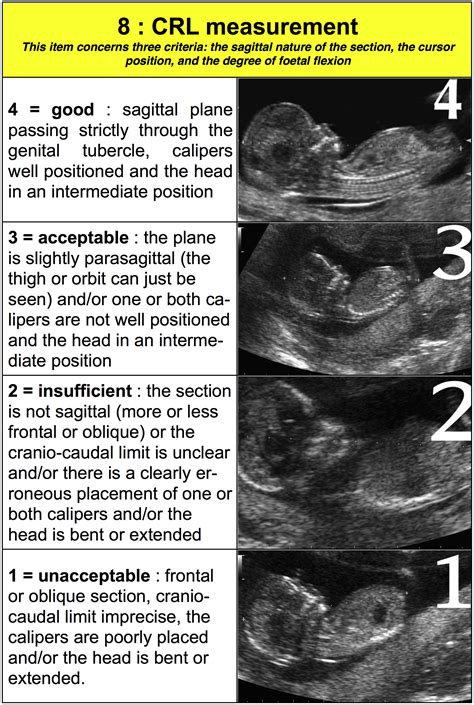

While the Crown Rump Length is considered the "gold standard" for pregnancy dating, its accuracy can be influenced by a few variables. Sonographer experience is paramount; if the calipers are placed incorrectly by even a millimeter, it can change the estimated gestational age by several days. Additionally, the position of the fetus matters—if the baby is hunched over or extended, the measurement might be slightly off. This is why a high-quality ultrasound image is essential for a precise reading.

During the scan, the sonographer identifies the top of the baby’s head and the bottom of the rump. They then use electronic calipers on the ultrasound machine to mark these two points. The software calculates the distance between them, and the computer instantly cross-references this value with gestational age databases to provide a measurement in millimeters (mm).